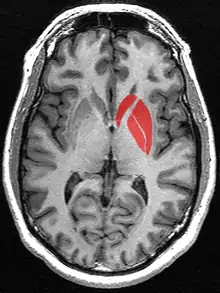

Striatum

Striatum (in red) shown within the brain

(pink: amygdala; blue: thalamus)